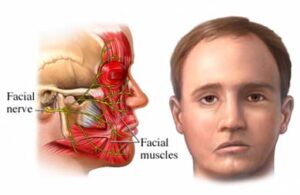

Paraliza faciale ose paraliza e fytyrës është një sëmundje që vjen nga demtimi e nervit të shtatë të kokës, i cili inervon muskujt e fytyrës

Shkaqet mund të jenë të shumta: traumatike (pas përplasjeve apo tërheqjeve muskulare), muskulare (në personat që punojnë gjatë në kompjuter ose në mjedise me ajër të kondicionuar), të lindura (nga problemet